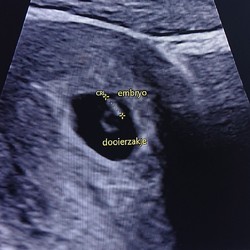

Weet iemand trouwens of het van je eigen risico afgaat?

Neee gaat niet van eigen risico af, maar als goed is moet je naast nipt ook niet andere dingen laten prikken, die gaan wel van je eigen risico af!